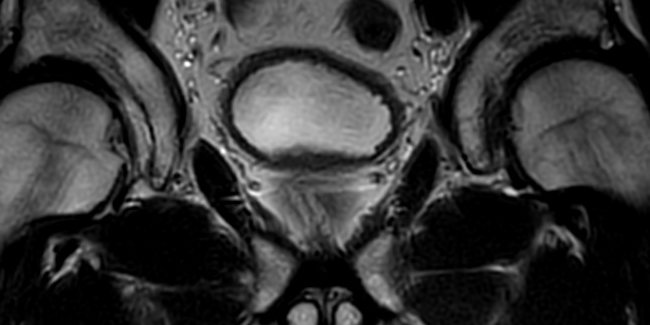

Nelle scansioni assiali si ha una buona visualizzazione: della parete e dei pannicoli grassosi anteriore posteriore e laterali della vescica, rapporti con le vescichette seminali o con l’utero.

Nelle scansioni coronali si ha una buona visualizzazione: della parete e dei pannicoli grassosi superiore inferiore e laterali della vescica, rapporti con l’utero o con la prostata o con le anse intestinali.

Nelle scansioni sagittali si ha una buona visualizzazione: della parete e dei pannicoli grassosi anteriore posteriore superiore e inferiore della vescica, rapporti con la prostata e vescichette seminali e retto o con l utero e la vagina.